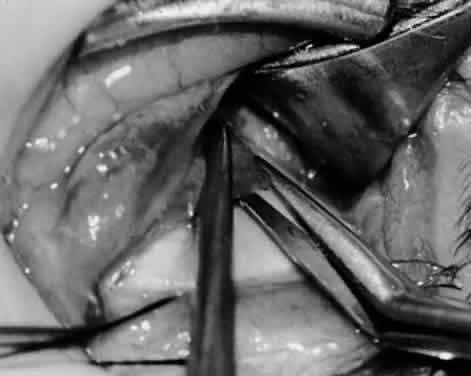

Fig. 11. Sutures are placed into the insertion of the inferior oblique muscle before it is sectioned from the globe for the recession procedure.

Fig. 12. An Aebli scissor is placed beneath the inferior oblique muscle insertion before it is sectioned from the globe.

Fig. 13. The inferior oblique muscle is sectioned from the globe. A preplaced 6-0 Vicryl suture is attached to the insertion.